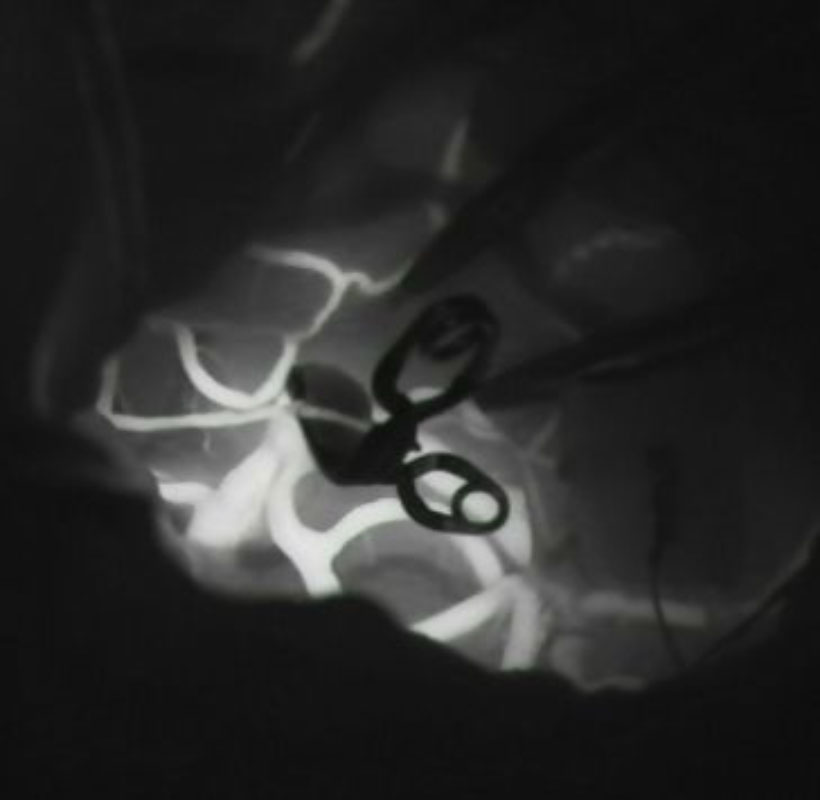

1

'26年1月

40代

右中大脳動脈瘤

クリッピング術

手術前

クリップ前

クリップ後

術後血管撮影